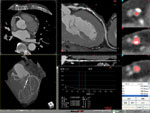

■ 冠動脈解析

更に進化した最新の冠動脈解析ソフトではデータの読み込みから冠動脈の抽出、CPR・ストレートビュー表示、アンギオ様のMIP処理までをフルオートで高速処理します。 |